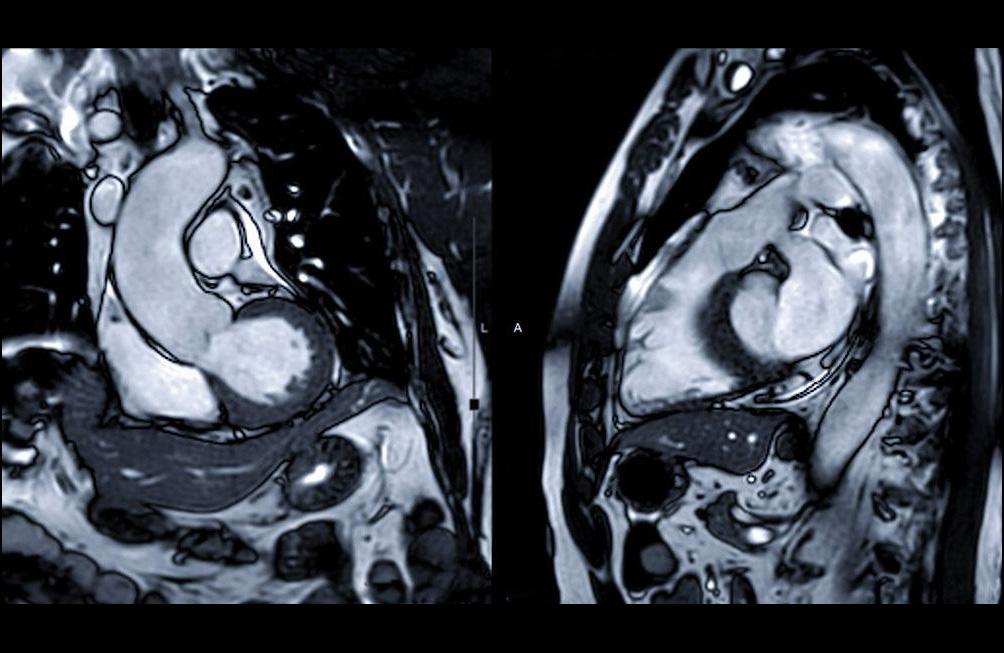

L'IRM cardiaque est une méthode sûre et non invasive, qui fournit des informations précieuses sur la structure et la fonction du cœur.

Elle est prescrite par un cardiologue et est généralement demandée en cas d'insuffisance cardiaque, de trouble du rythme, de myocardite ou de myocardiopathie.